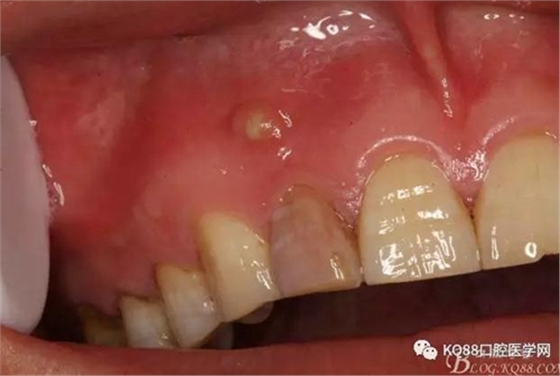

一個(gè)月后患者復(fù)查: 唇側(cè)觀:11根尖區(qū)粘膜有一膿瘺,捫診溢膿,牙冠成灰褐色。根管治療無(wú)法治愈根尖病變,建議根管外科治療,患者同意手術(shù)。